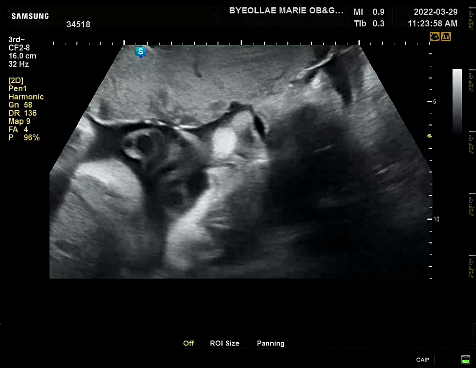

초음파 영상을 보면 까꿍이가 계속 눈을 뜨고 있는 것을 볼 수 있다. 원장샘 말로는 눈 꽤나 오랫동안 뜨고 잘 놀고 있다고 하셨다. 덕분에 장모님도 까꿍이의 모습에 더욱더 생동감을 느끼고 교감하였다고 했다.

두 손으로 얼굴을 가리고 있어서 얼굴 윤곽이 또렷이 나오진 않았지만, 그래도 눈 뜨고 하품도 하고 해서 너무나 귀여웠다. 이전 기록과 비슷하게 주수에 비해 머리둘레는 살짝 크고, 배 둘레, 다리 길이, 체중은 살짝 미달이었다. 체중도 1.8kg 평균주수 대비 살짝 적지만 작은 아가로 태어날거라 생각한다. 그래도 까꿍이 3kg는 찍자꾸나! 화이팅!!!!